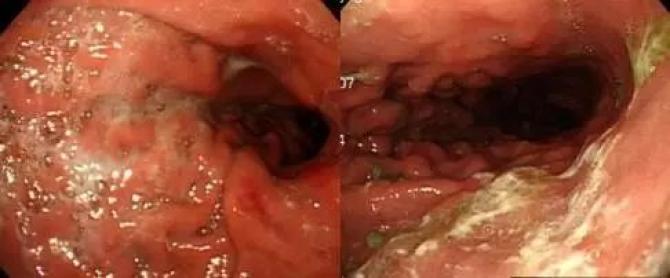

2、与普通胃镜相比,术前准备更充分。普通胃镜检查,虽然患者是空腹状态,但胃肠道内有较多粘液及泡沫不能完全消除,影响内镜下观察效果。胃镜精查检查前15-30分钟,给予患者黏液溶解剂及祛泡剂以完全清除上消化道内黏液与气泡,有效改善视野清晰度,大大提高微小病变的检出率,见图。

有时需要在胃镜下对食管、胃、十二指肠黏膜进行地毯式搜索,一旦发现可疑病灶,再针对性地进行染色、放大、精准活检等手段,使消化道内的各种组织看得清清楚楚(如微血管网结构、微腺管结构等)。